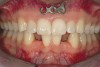

Figure 5a  A 22-year-old female presented, concerned about smile, overbite, and baby tooth. Facial views reveal excellent skeletal components with excessive gingival display and insufficient lip support. Anterior deep bite with extruded and retruded anterior dentition secondary to unstable relationship.

Figure 5a

Figure 5c  Note lack of alveolar development from congenitally missing Nos. 24 and 25. Surgical procedures after 5 months of orthodontic alignment included single-tooth osteotomies Nos. 6 to 11 and Nos. 21 to 28 and buccal corticotomies on all other teeth. Anchorage plate was stabilized to piriform rim.

Figure 5c

Figure 5e  Anchorage plate was stabilized to piriform rim (E through H). Final result 12 months postsurgery (F). There is significant lateral dentoalveolar expansion of arches and alveoloskeletal correction in maxillary and mandibular anterior regions. Alveolar bone volume was increased in lower anterior to create optimal implant sites and establish ideal interincisal function and stability.

Figure 5e